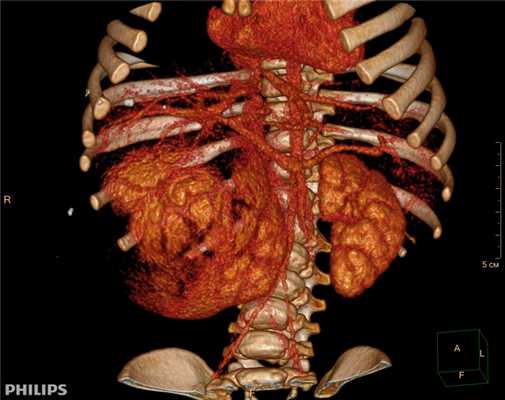

Компьютерная томография более детально дает информацию об анатомическом отношении опухоли к окружающим тканям и органам, позволяет оценить структуру опухоли (рис. 5).

Рис. 5. КТ нейрогенного образования забрюшинного пространства справа